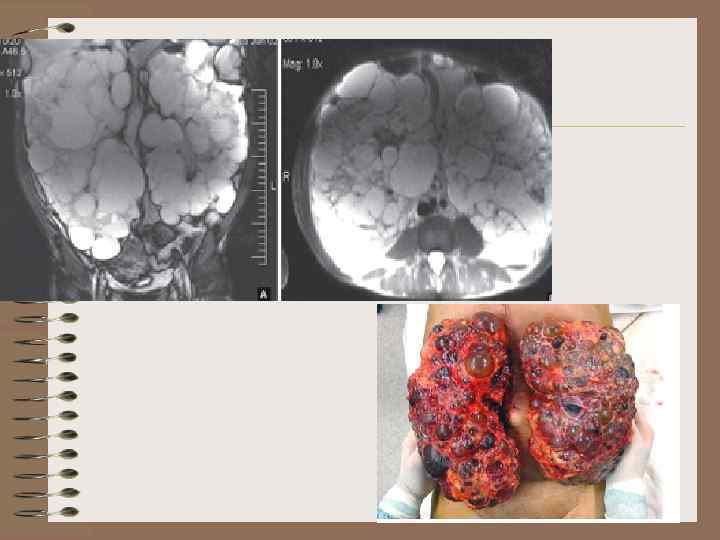

Поликистоз, взрослый тип

Поликистоз взрослых. МРТ Асимметрия объема изменений почек